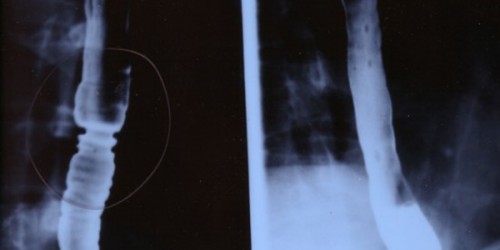

No wonder tranquilizers only work for your troubles. This usually works for muscle contractions and it is exactly what it is happening. Nutcracker esophagus presents abnormalities in swallowing contractions. Contractions appear in a coordinated manner, but their amplitude is excessive and powerful.

Most of the nutcracker esophagus cases are caused by gastroesophageal reflux.

Medical treatments include drugs like calcium channel blockers, tricyclic antidepressants, nitrates, botulinum toxin, and dilatation. Nutcracker esophagus is not a progressive disorder but it can be quite annoying and visibly impair the patient's quality of life.